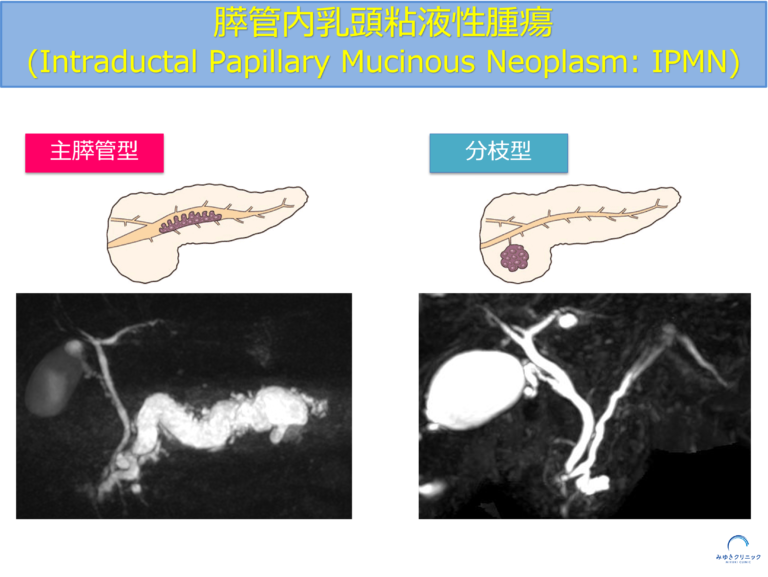

IPMNの種類(主膵管型・分枝型・混合型)

IPMNは、発生する場所によって大きく3つのタイプに分類されます。

IPMNは発生する場所によって、主膵管型・分枝型・混合型の3つに分類されます。

IPMNの種類とリスクの違い

■ 主膵管型IPMN

膵臓の中心を通る主膵管に発生するタイプで、悪性化のリスクが高いとされています。

■ 分枝型IPMN

膵管の枝に発生するタイプで、比較的悪性化のリスクは低く、多くは経過観察となります。

■ 混合型IPMN

主膵管型と分枝型の両方の特徴を持つタイプで、慎重な評価が必要です。

このように、IPMNはタイプによってリスクが異なるため、それぞれに応じた経過観察が重要になります。

どのタイプかによって、経過観察の間隔や検査法、治療方針も変わります。